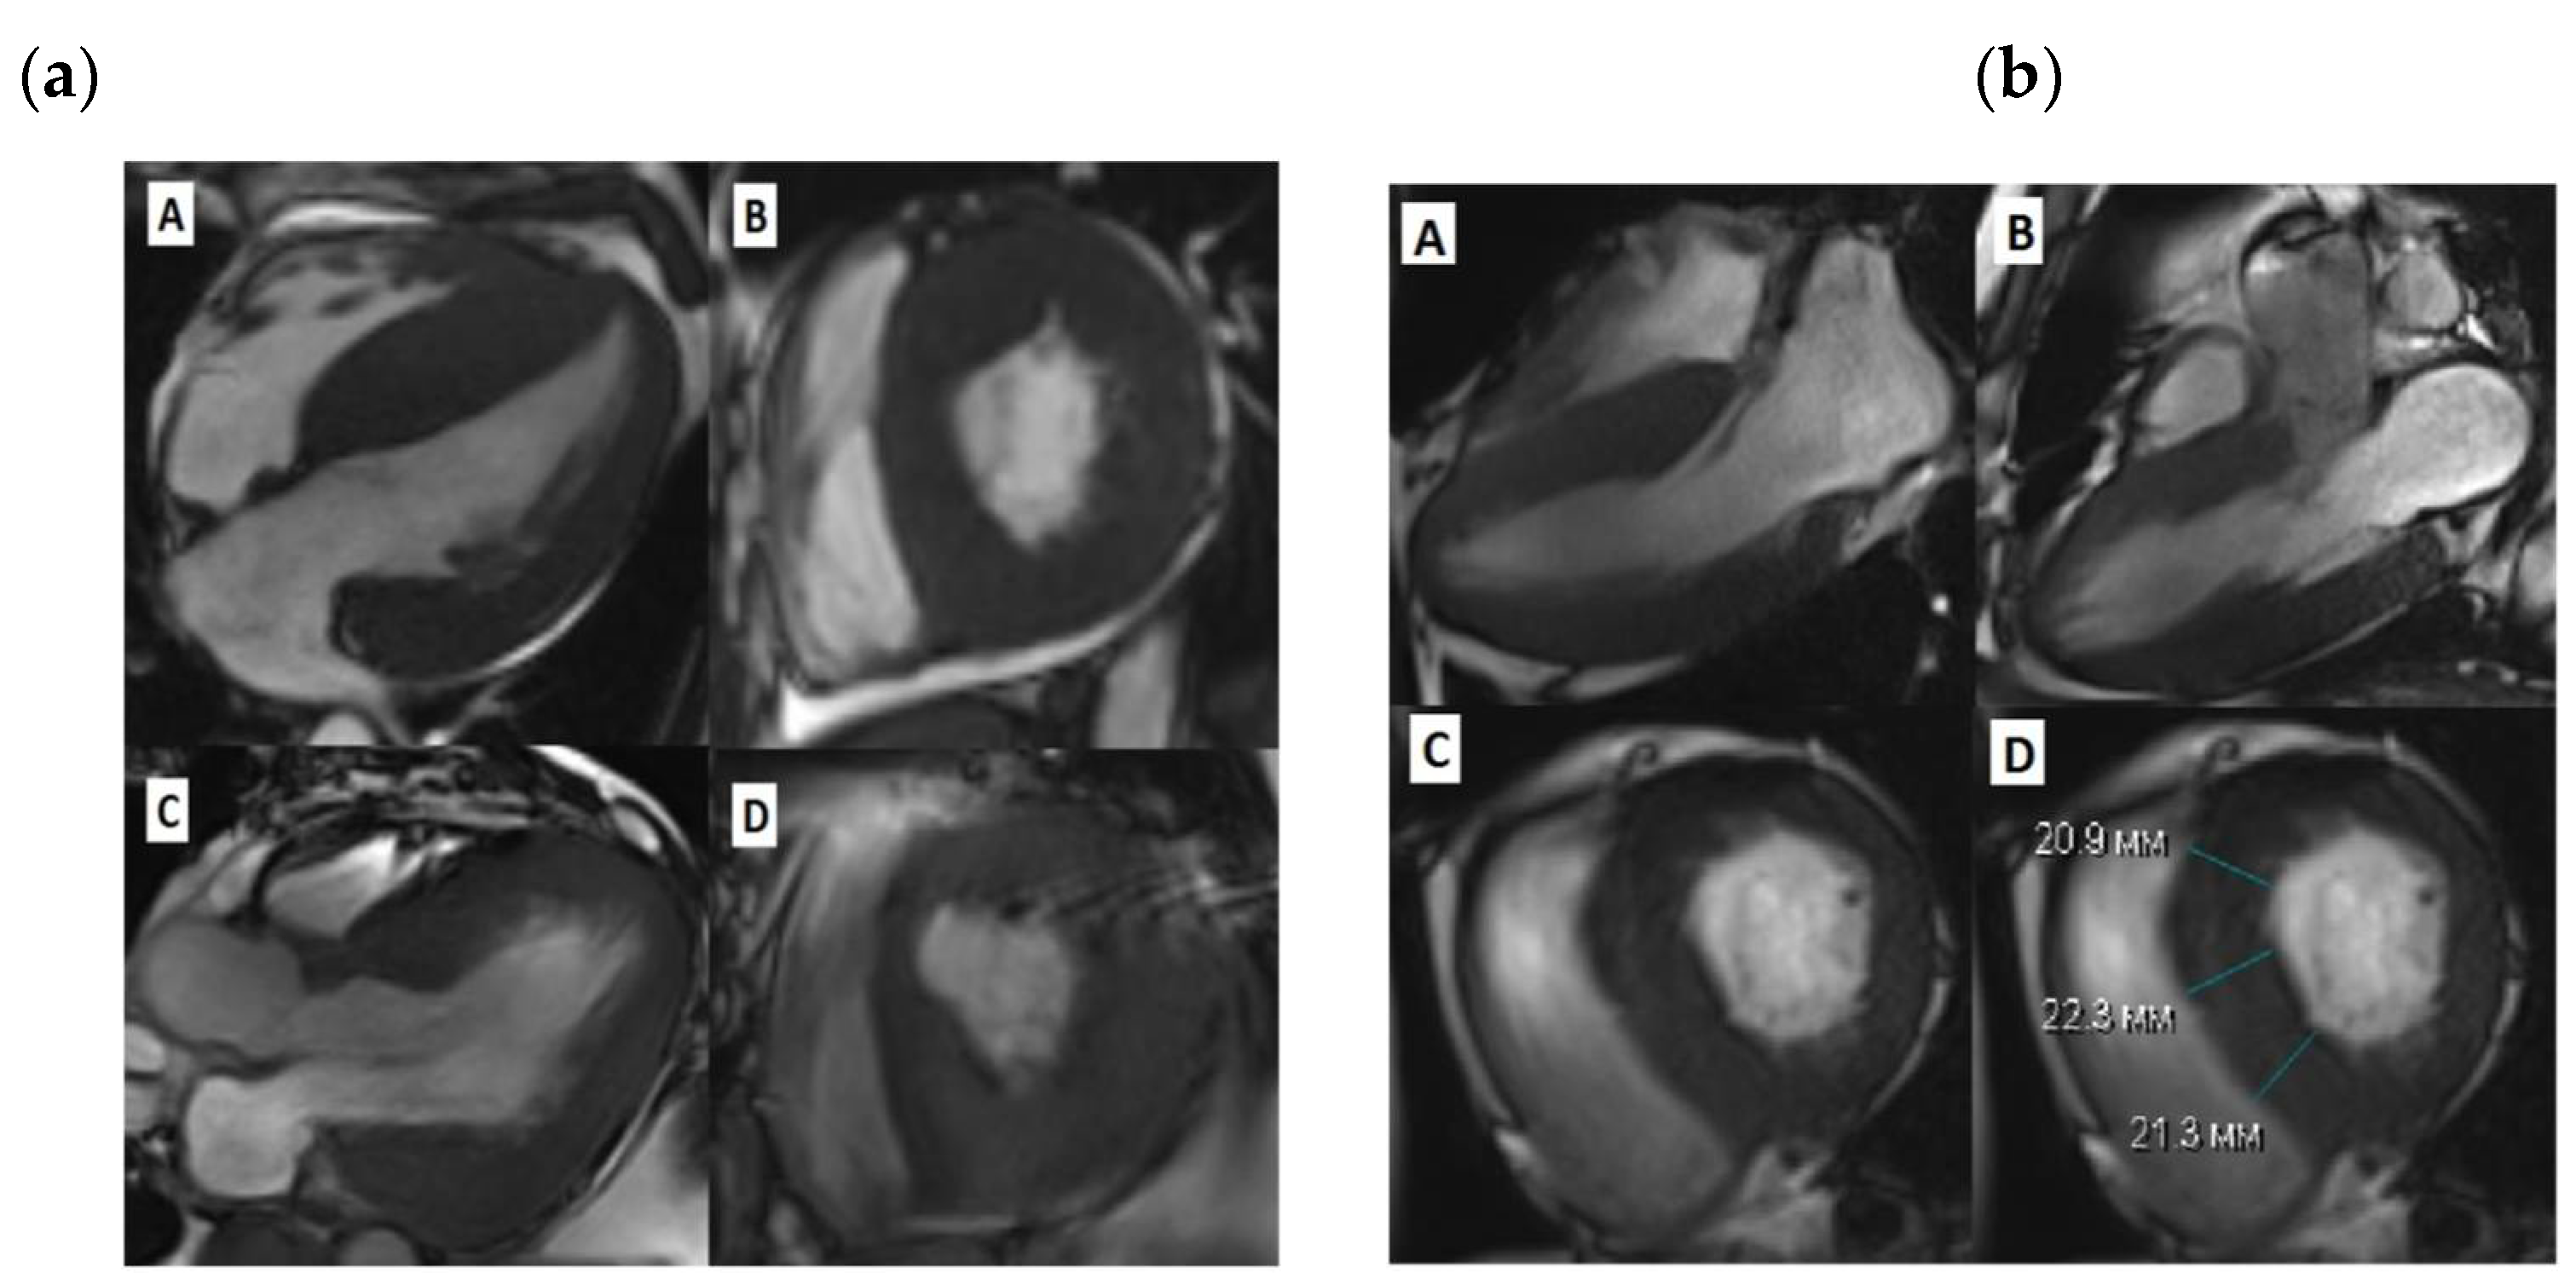

Figure 1. Cardiac MRI before and after SSM. (a)-Patient 1, A-diastolic view before SSM, long LV axis, B- diastolic view before SSM, short LV axis, C -diastolic view after SSM, long LV axis, D-diastolic view after SSM, short LV axis; (b)-Patient 3, A, B-diastolic view before SSM, long LV axis, C,D -diastolic view before SSM, short LV axis;.

Three patients were enrolled in Almazov National Medical Research Centre during 2016-2022 to perform SSM due to obstructive form of HCM without previously known diagnosis of ADF disease. The main clinical characteristics of patients are summarized in Table 1. In all patients, standard clinical examination including echocardiography and Holter ECG monitoring were performed prior to cardiac surgery. MRI images were obtained using ultra-high field tomography Magnetom Trio A Tim 3,0 Тл (Siemens) with 8 mm slices using Gd-DO3A 0,2 ml/kg contrasting. Of note, two out of three patients underwent non-ST MI prior to operation and one of them had classical angina without any intracoronary obstruction according to angiography. In one patient a pacemaker was implanted due to II-degree AV-block (type 2). Nobody of the patients revealed ventricular tachycardia, while all three presented with premature ventricular contractions grade III-IV Ryan. All patients revealed various degree of myocardial fibrosis according to MRI either in bother ventricles (Patient 1), in IVS and LV (Patient 2) or solely in left ventricle (Patient 3). Only Patient 1 had increased right ventricular thickness. All surgical procedures were performed with cardiac arrest under retrograde Calafiore blood cardioplegia according to B. Messmer modification [13]. In one case (Patient 1) vena cava superior was dissected in order to verticalize interventricular septum due to poor visualisation. In Patient 3 mitral second-order chordae resection of anterior mitral valve leaflet was performed [14]. All three patients had no postsurgical complications and were discharged at day 14-16 with remarkable clinical and subjective improvement (CHF class I-II and no signs of angina). Morphological examination confirmed extensive fibrosis and disarray.